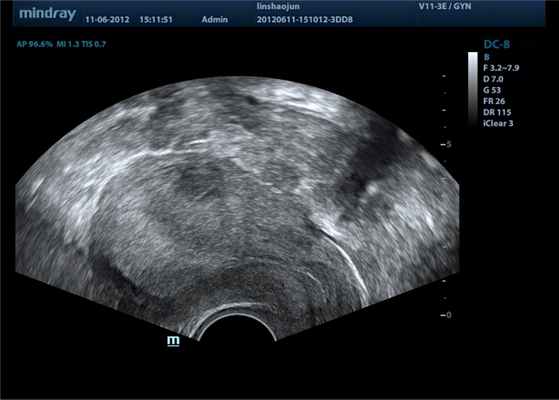

В-режим (B – brightness) – режим двумерного серошкального сканирования. Является основным режимом для получения диагностической визуализации органов, тканей, стенок сосудов и внутрипросветного содержимого. Получение изображения в B-режиме основано на эффекте отражения ультразвука от границ сред исследуемой области: прибор УЗД анализирует амплитуду и фазу отраженного эхосигнала, данная информация участвует в процессе построения изображения (которое в последствии выводится на экран прибора) и обуславливает яркость свечения и положение пикселя на диагностическом изображении.